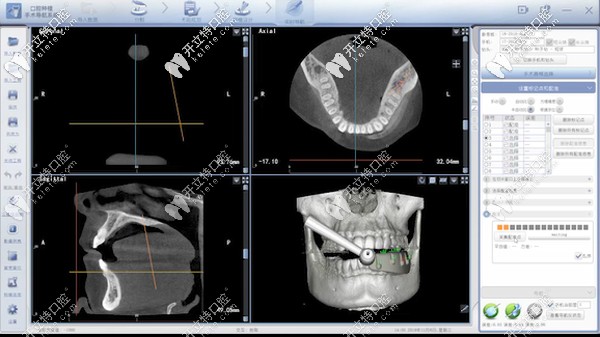

據(jù)了解:口腔種植數(shù)字化動(dòng)態(tài)導(dǎo)航是種植牙當(dāng)中的黑科技,主要通過計(jì)算機(jī)重建患者口腔頜骨三維立體模型。

它就像汽車導(dǎo)航一樣,通過顯示屏實(shí)時(shí)直觀地看到種植體植入頜骨的全過程,全程監(jiān)控種植位點(diǎn)、角度、深度。

能夠避免損傷重要的解剖結(jié)構(gòu),給患者提供更加安全、精準(zhǔn)、高效的體驗(yàn)。